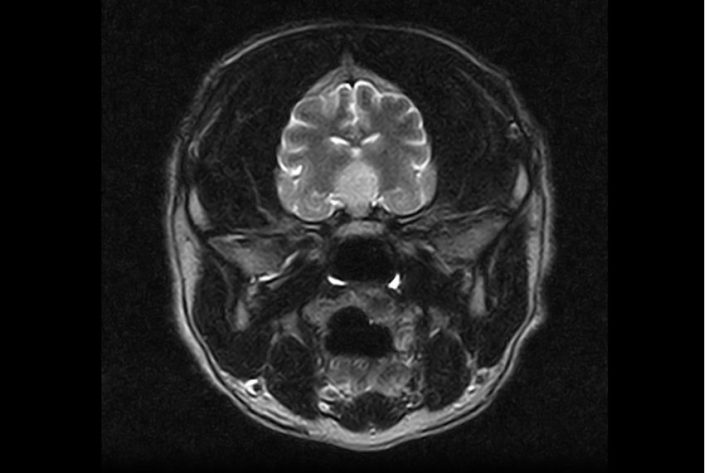

Bildgebende Diagnostik: Mittels Ultraschall werden vor allem die Nebennieren angeschaut (Vergrößerung, Tumor). Ein CT des Bauches kann vor allem bei großen Hunden indiziert sein, da die Nebennieren mittels Ultraschall oft nur eingeschränkt beurteilbar sind. Schließlich kann ein MRT den Verdacht auf einen Hirntumor bestätigen. Allerdings können Hypophysentumore auch vorhanden sein, ohne dass sie im MRT sichtbar sind.

Magnetresonanztomographie - Aufnahme des Schädels

Hyperadrenokortizismus MRT